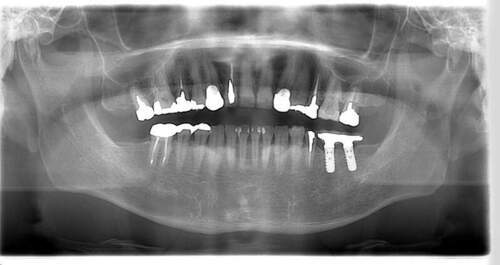

インプラント治療の症例2

レントゲン写真

- Befor

- After

| 年齢 | 50代・男性 |

|---|---|

| 主訴 | 左上7番 左下5番7番 |

| 治療内容 | ・インプラント埋入 ※1:GBR(骨造成)・・・骨再生誘導法。骨の高さや厚みを人工骨や人工膜などを使用し再生する方法 |

| 治療費 | 合計:1,809,500円(税込) ■内訳 ・左上7番 ・左下5番7番 |

| 治療期間 | 左上7番約1年 左下5番7番約10ヵ月 |

| 治療方針 | 左上7番は昔他院で被せものをしており、被せものの中が歯ぐきの中まで虫歯になっていたため抜歯せざるを得ない状態だった。抜歯と同時に骨造成を行い、骨が出来るまで4ヵ月待ってからインプラントを埋入した。 ※2ポンティック・・・歯のない部分を補うダミーの歯。 |

| 担当者所見 | 元々金属の被せものが多く入っていたため、2次カリエス※3が多かった。今回は金属ではなく、ジルコニアを使用し、2次カリエスにならないよう、患者様にはブラッシング指導とメンテナンスの重要性をお伝えした。 ※3二次カリエス・・・詰め物や被せものを入れた歯が虫歯になること。 |